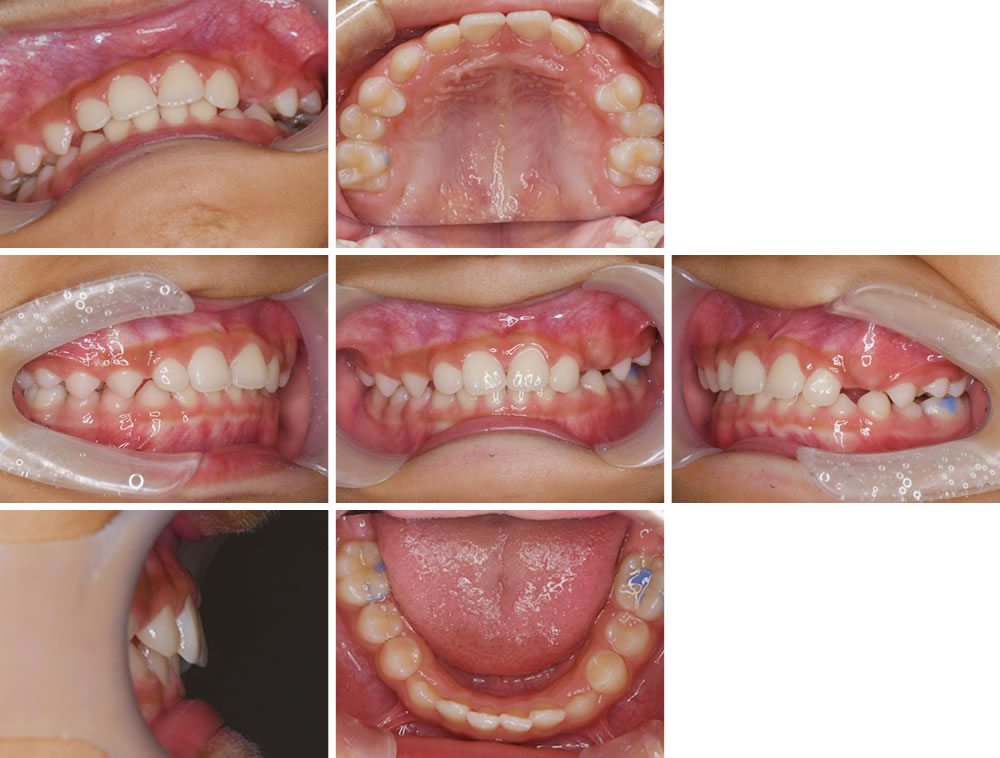

治療完了

治療完了時の状態です。顎の拡大、歯並びが改善されました。